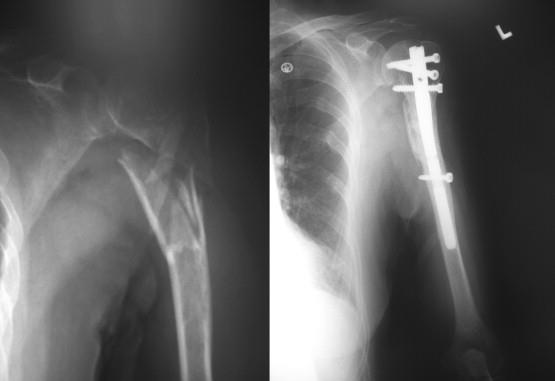

[Blocked from Release] T2 Alpha® Humerus Nailing System

• The T2 Alpha® Humerus Nailing System is an intramedullary fixation system designed for stable treatment of humeral shaft and proximal humerus fractures

• Allows minimally invasive insertion with multiple locking options to enhance rotational and axial stability

• Short nail

• diameter: Ø8mm

• length: 150mm

• Long nail

• diameter: Ø7mm–Ø10mm in 1mm increments

• length: 180-315mm in 15mm increments